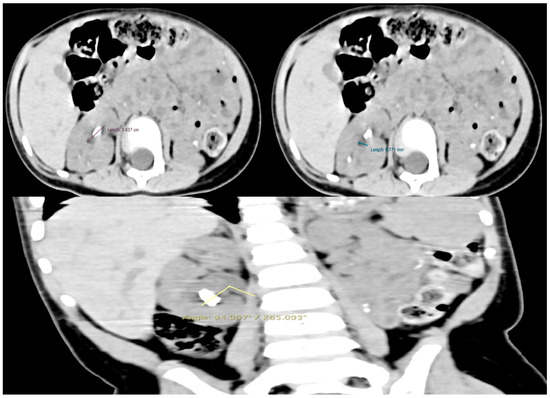

A non-contrast low-dose kidney–ureters–bladder (KUB) computed tomography (CT) was performed, reporting six stones in the right kidney of the patient with a cumulative stone burden of 3.2 cm2 (two stones per calyx without filling the pelvis). The largest stone was located in the upper calyceal system, measuring 10 × 14 mm and 810 Hounsfield units (HUs) (Figure 1 and Figure 2).

Figure 1. The preoperative CT scan of this case showing the stones in the right kidney. (A) Axial view of the upper pole stone, (B) coronal view of the upper pole stone, and (C) coronal view of the upper pole and middle pole stones. The stones are marked with red arrows.